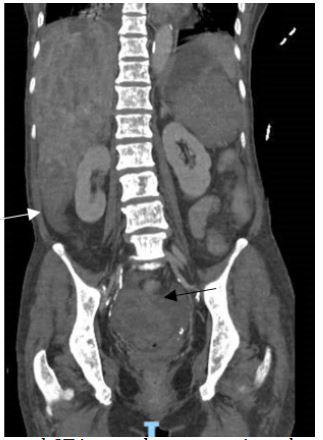

Figure 2: Coronal CT image showing extensive sclerotic bone metastases.

Figure 5: Coronal CT image demonstrating a large haematoma inferior to the liver (white arrow) and within the pelvis (black arrow), secondary to a ruptured, haemorrhagic liver metastases.